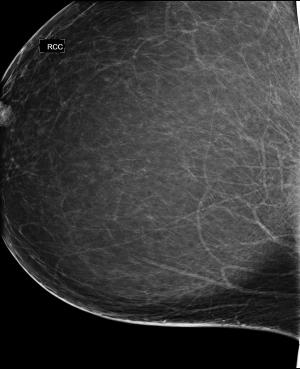

45-year-old female with abnormality on routine screening mammogram, underwent breast reduction surgery 2 years prior.